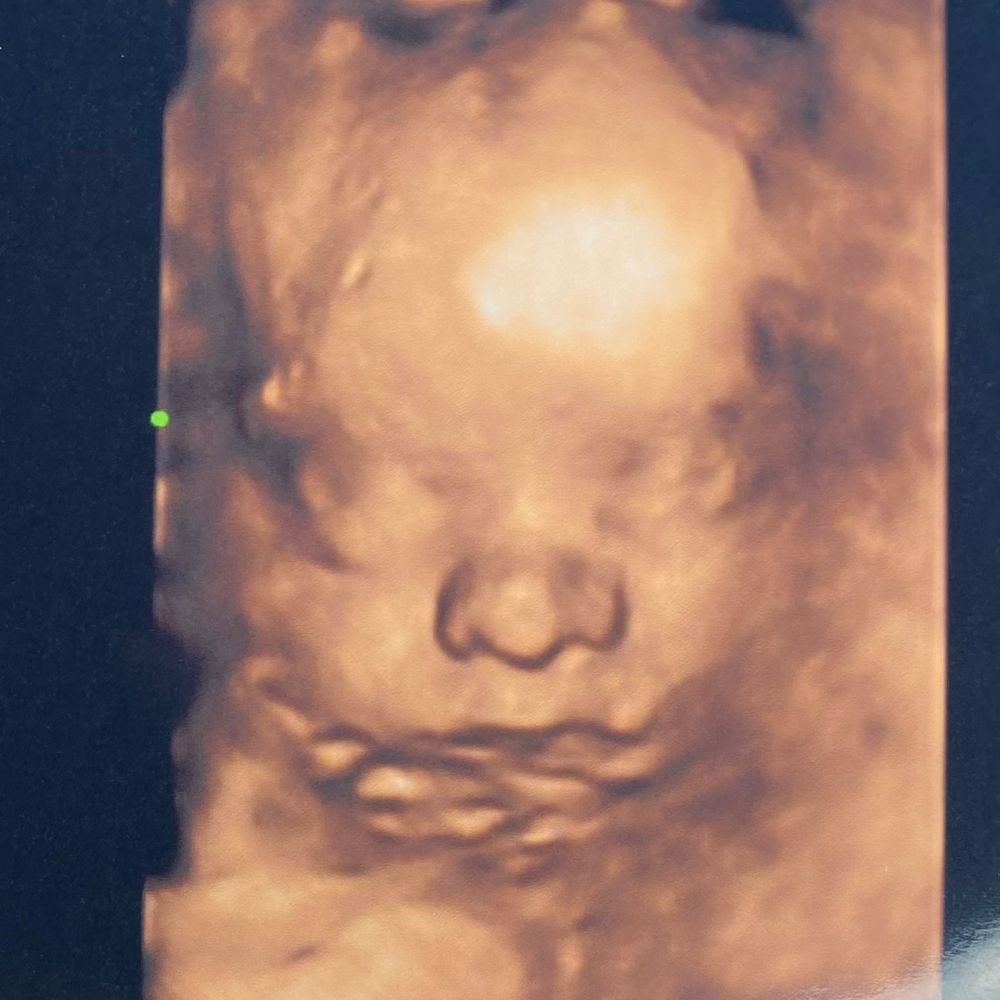

29+1, 3д узи

Голова у плаценты как на подушке, играет с пуповиной, тянет ее в рот, хватается за мыски ног. Хорошо ему там на попе сидится, сегодня начну стоять в коленно-локтевой в надежде, что перевернётся.